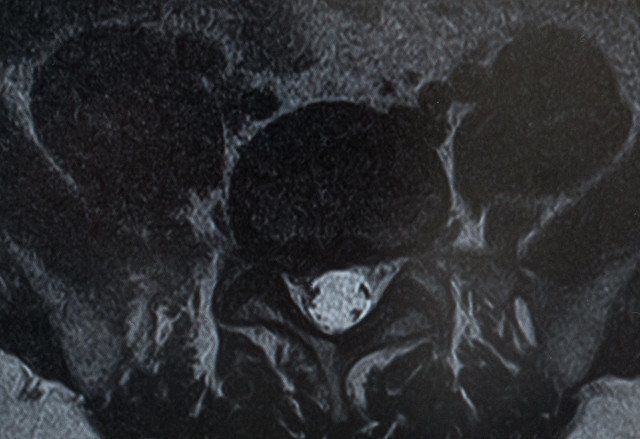

• 腰部脊柱管狭窄症

脊柱管は背中の中央を貫く[神経の通り道]です。

この脊柱管が腰の所で何らかの原因で狭くなり中を通っている神経が圧迫されることによって腰痛やシビレを起こします。

• 腰痛分離・すべり症

腰痛すべり症とは椎骨が前方にずれた状態で腰痛すべり症と腰椎分離すべり症がある。